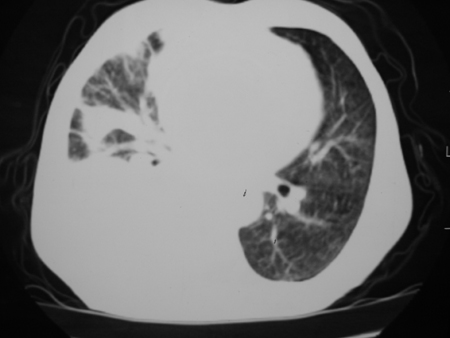

男77岁,胸痛就诊

右侧胸腔积液,部分包裹,右下肺膨胀不全,右下肺感染。

考虑右肺门占位并下叶不张 右胸包裹积液

右侧胸腔积液,部分包裹,右下肺膨胀不全

右肺中叶及下叶炎症并胸腔积液(部分包裹),建议抽液后复查ct除外占位。